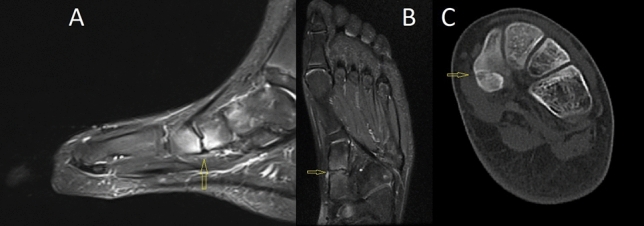

Fig. 10.

CT and MRI of left feet. A Sagittal MRI of medial cuneiform–navicular coalition demonstrates at the periphery of coalition adjacent edema. B Coronal MRI medial cuneiform–navicular coalition. C CT image of medial cuneiform–navicular coalition

Lateral view of the left foot demonstrates lengthening of irregularities of the cuneiform bones and navicular borders, suggestive of cuneiforms–navicula coalition (Fig. 9). Sagittal CT image revealed an osseous medial cuneiform–navicular coalition on left side. Sagittal and axial MRI revealed an osseous medial cuneiform–navicular coalition. T2-weighted with fat suppression images demonstrate at the periphery of coalition adjacent edema (Fig. 10). Secondary osteoarthritic changes were not identified.